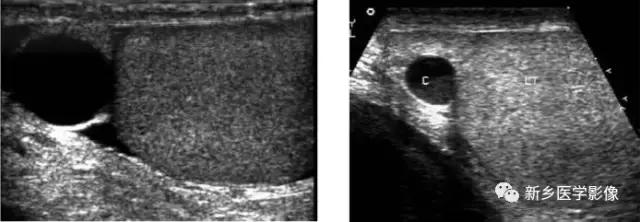

附睾囊肿 先天性病变,常于附睾头部探及一圆形无回声区,囊壁薄,光滑,直径从数毫米至数厘米,多在1cm以内,少数可长得很大。精液囊肿囊内可见细点状回声。附睾囊肿少数位于体尾部。精液囊肿比单纯囊肿T1WI信号高。

*丸睾**囊肿 表现为*丸睾**内圆形无回声区,囊壁薄,光滑,内透声好。磁共振信号均匀,无强化

*丸睾**鞘膜积液:阴囊内*丸睾**周围可见液性暗区环绕,如阴囊上下极同时出现积液,可作出诊断。

精索鞘膜积液:液性暗区位于腹股沟区精索内,两端封闭,不与腹腔及*丸睾**鞘膜相通。

交通型鞘膜积液:鞘膜内液体可流入腹腔,液性暗区体积可变化,站立位时较大,仰卧位时可变小。

婴儿型鞘膜积液:*丸睾**鞘膜积液可能和精索鞘膜积液同时存在,但与腹腔不相通。